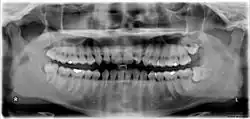

A = Retinierter Weisheitszahn 48 mit mesialer Karies;

B = distale Karies am Zahn 47, dazwischen Gingivitis;

C = entzündete, künstliche Zahnfleischtasche;

D = Elongierter Zahn 18

Die folgenden Röntgenbilder sind Ausschnitte aus Orthopantomogrammen (OPG):

-

Weisheitszahn 38; retiniert und verlagert; mesiale Kippung um fast 90°

Weisheitszahn 38; fast bis zur Kauebene durchgebrochen; distale Wand vollständig im Knochen; voll ausgebildete Wurzel; Wurzelspitzen projizieren sich auf den Nervus alveolaris inferior

Weisheitszahn 38; retiniert und verlagert – stark nach mesial gekippt; sehr kurze Wurzelspitzen projizieren sich auf den Nervus alveolaris inferior

Weisheitszähne 48 und 18; Zahn 48 – keine Kippung, Wurzel nur teilweise ausgebildet, Krone teilweise noch knöchern bedeckt

Weisheitszahn 38 angelegt; retiniert – Krone unter Zahn 37 verkeilt; Krone okklusal nicht mehr von Knochen bedeckt; nur eine Wurzel sichtbar – relativ kurz aber voll ausgebildet.

Weisheitszahn 38 angelegt – fast noch keine Wurzel ausgebildet; mesial gekippt.